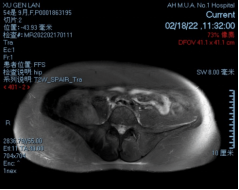

术前影像

穿刺活检提示骨盆软骨肉瘤

日前,安医大一附院骨病骨肿瘤外科胡勇教授团队成功完成一例复杂骨盆Ⅰ+Ⅱ+Ⅲ+Ⅳ区肿瘤切除与3D打印组配式半骨盆假体重建手术。患者为女性,53岁,下腰痛半年余,右侧臀部膨隆,右侧下肢轻度浮肿。右侧髂棘髂窝及臀部可触及巨大肿物,压痛明显,右髋外展前屈活动受限,右侧大腿感觉麻木,右足感觉运动正常。骨盆肿瘤切除重建是骨科专业中难度极大、风险极高的手术。骨盆肿瘤约占原发骨肿瘤的3%~4%,其中以软骨系统肿瘤最为多见,其次为骨巨细胞瘤、成骨肉瘤等,儿童尤文肉瘤亦好发于骨盆。